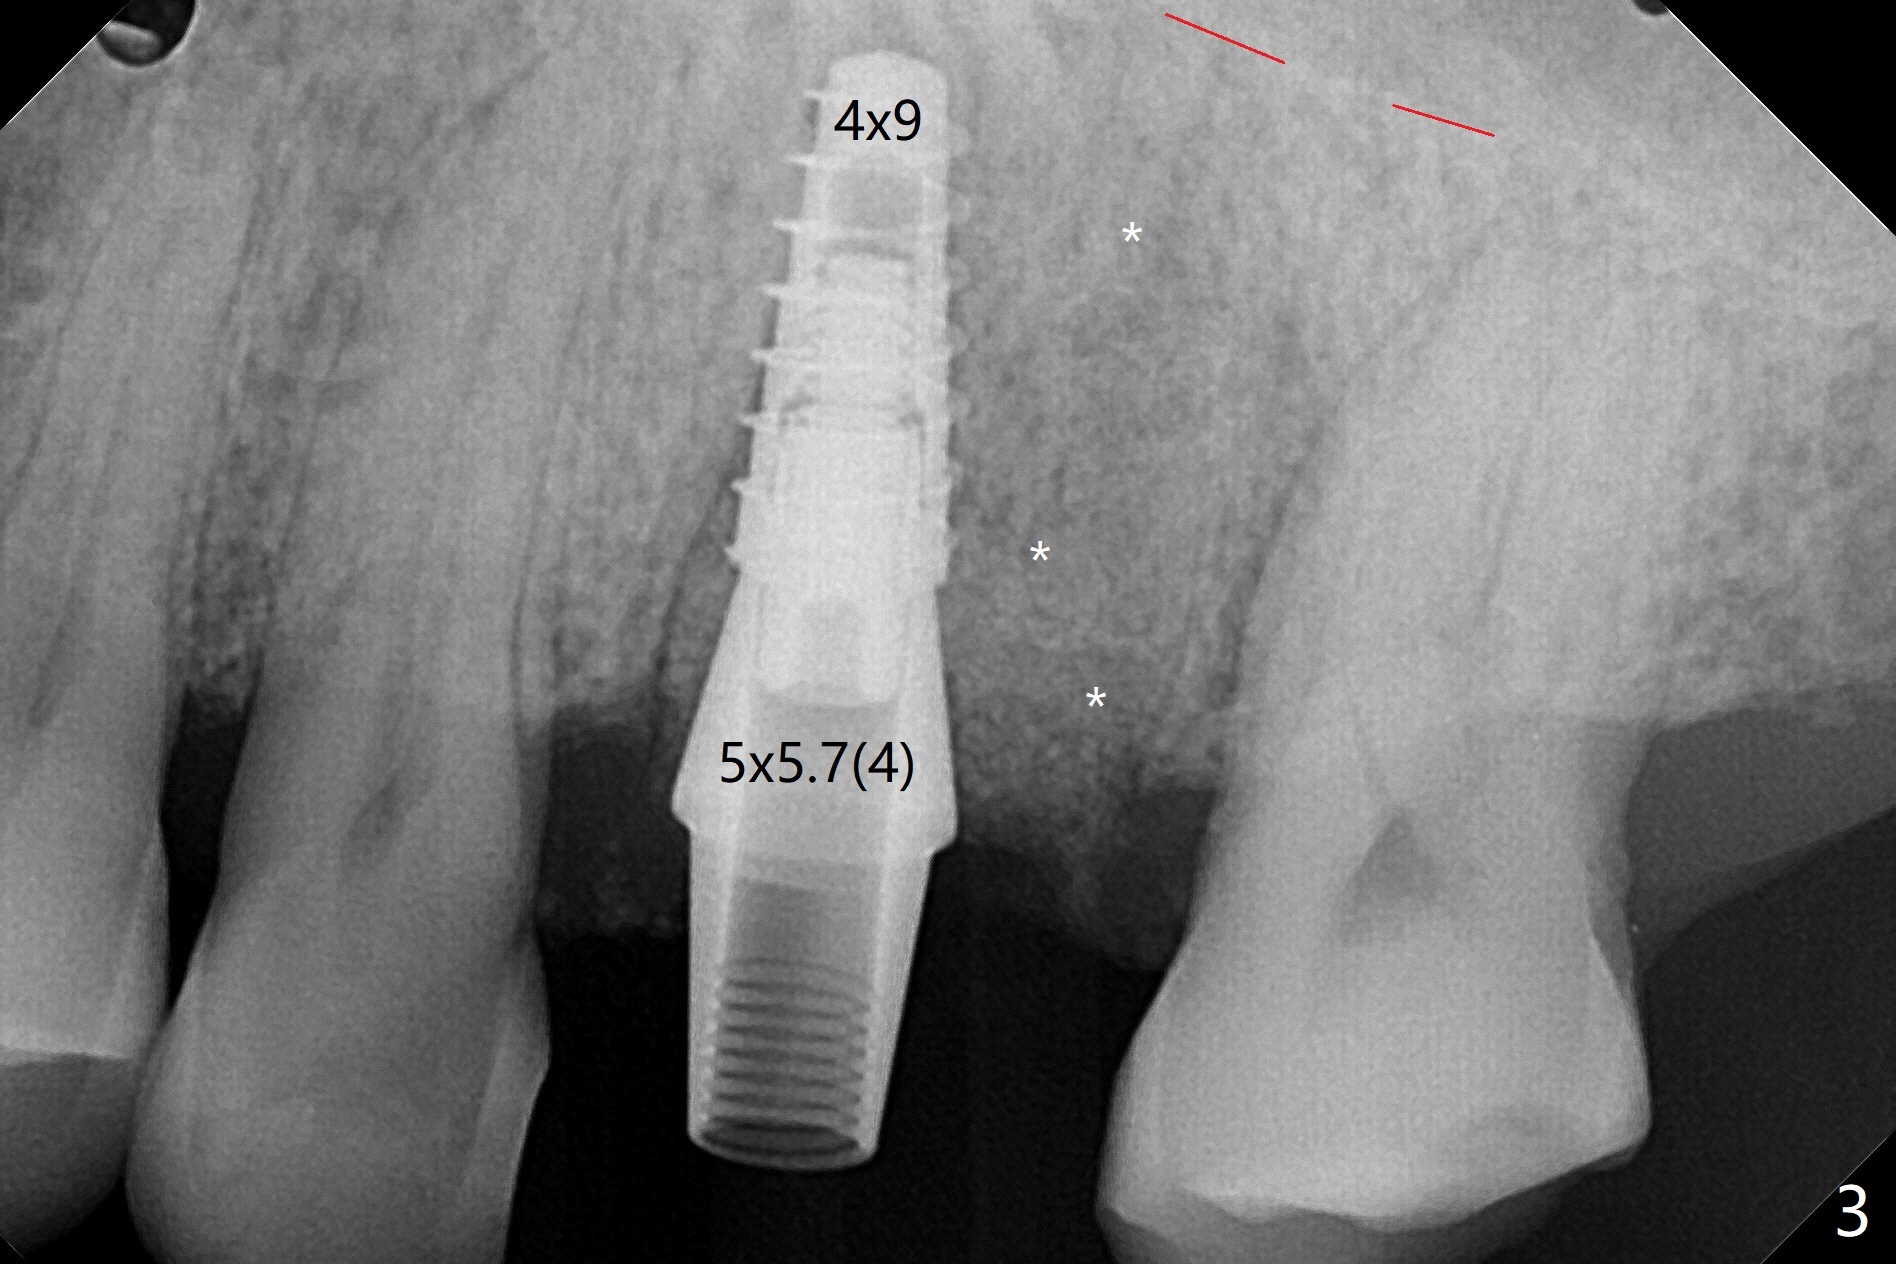

尽管14号牙远中裂纹(图一:箭头),冷热痛,拔除时腭侧根表面覆盖结石,似乎没有牙周膜附着。虽然牙龈萎缩不明显(图二:箭头),拔除后检查显示腭侧骨板缺失一直到根尖。使用10.5 和12毫米bone trimmers后中隔平面偏向近中,使用设计最后一个钻头(3x10mm)后,钻洞已经进入近中颊侧牙槽窝,由于植入4x9毫米植体扭力高于35 Ncm,使用3.5x7.3,3.5x8.5毫米钻头(也可以减少植体腭侧偏移)后,扭力20Ncm(图三),腭侧一个螺纹暴露。放置基台后,填入粘性骨粉(*),远中颊侧牙槽窝可能与腭侧牙槽窝重叠。制作临时牙冠,衬里,取出牙冠,覆盖PRF后,盖上牙冠,检查牙冠与对合牙分开~1毫米。术后一周临时牙冠与腭侧牙龈接触紧密,覆盖巨大腭侧缺损。如果没有临时牙冠,关闭腭侧缺损谅必困难,可能出现骨粉暴露。